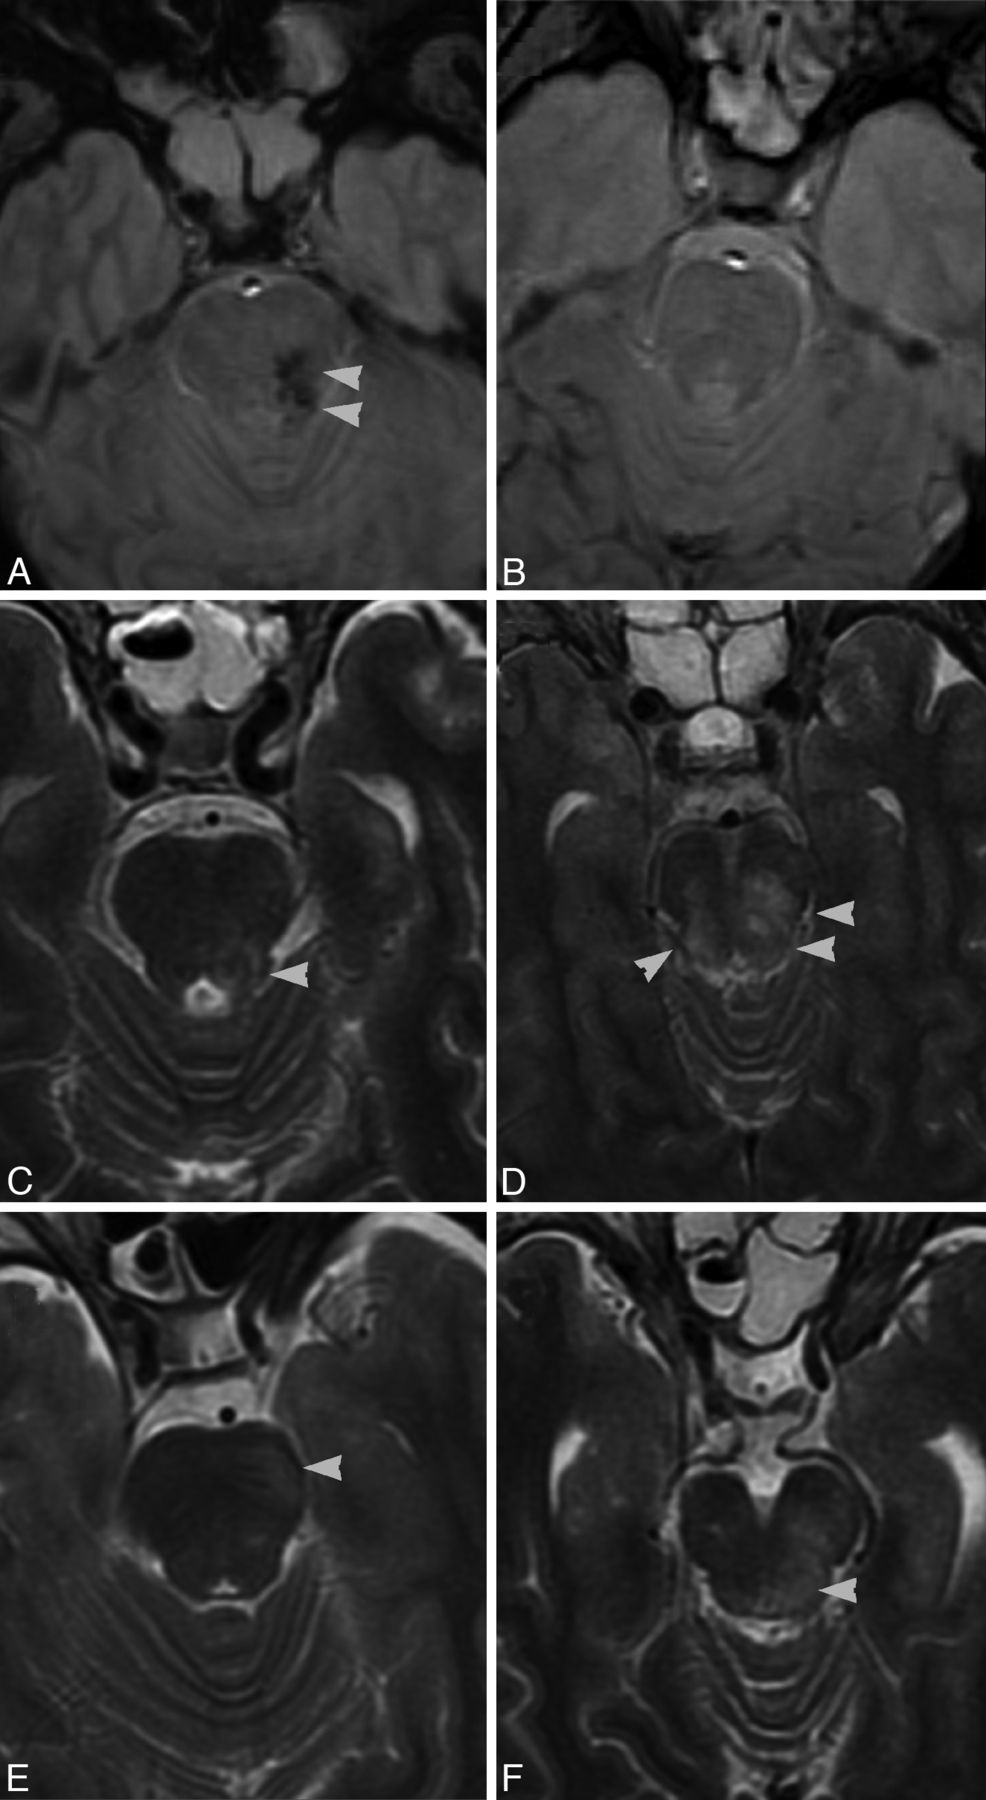

Two independent neuroradiologists, blinded to the neurologic condition of patients, reported brain stem injuries based on visual inspection. Brain stem lesions were classified as 1) anterior or posterior, 2) unilateral or bilateral, and 3) hemorrhagic or nonhemorrhagic. According to location, central lesions were classified in the group of anterior injuries. Based on injury characteristics on conventional imaging sequences, nonhemorrhagic lesions were defined as areas of increased signal intensity on T2 and FLAIR, and hemorrhagic injuries were described as foci of decreased signal on gradient-echo T2. Findings were also classified as unilateral or bilateral lesions, according to the involvement of the brain stem. Illustrations of the different brain stem injuries are shown in Fig 1.

Illustrations depicting the different types of brain stem injury observed with subacute MR imaging in severe traumatic brain injury. Gradient-echo T2 images in the axial plane show hemorrhagic (A) (hypointensity indicates foci of hemosiderin deposition) and (B) nonhemorrhagic diffuse axonal injury. On the other hand, axial T2-weighted images demonstrate unilateral (C) and bilateral (D) brain stem traumatic involvement, as well as anterior (E) (contusion) and posterior (F) (diffuse axonal injury) location in the brain stem.